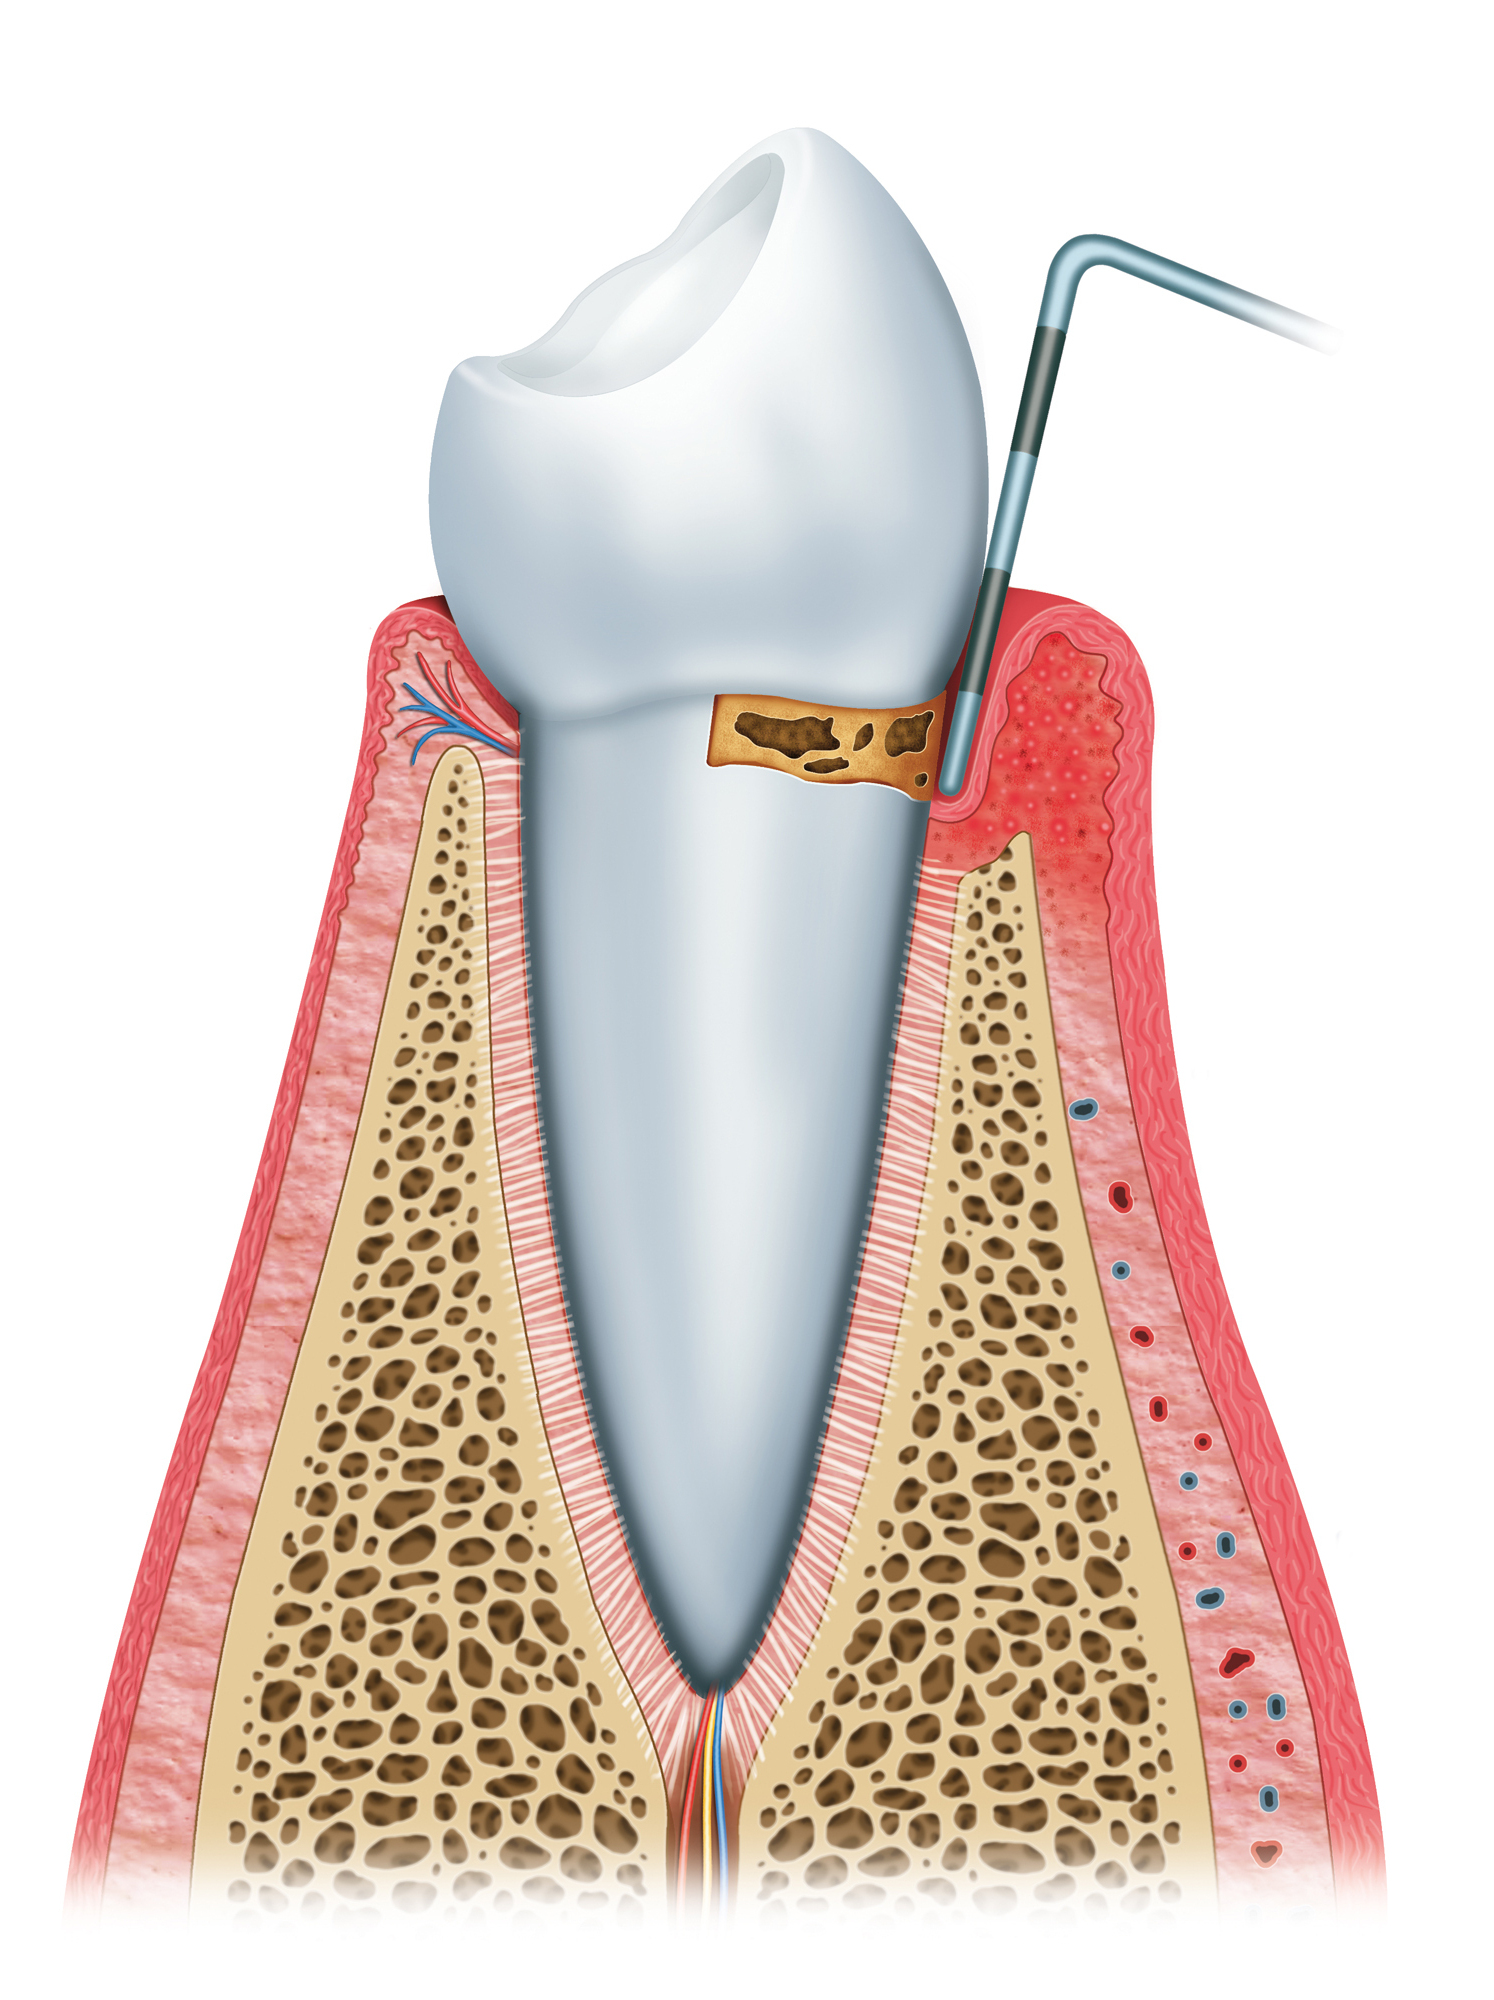

此階段細菌已侵入齒槽骨,造成齒槽骨流失,並破壞牙周韌帶,使牙齦與牙齒之間形成一條狹窄的縫隙,稱為牙周囊袋。一旦牙周囊袋產生,牙菌斑就更容易在此堆積,牙刷將很難清潔到此處的死角,牙齦紅腫發炎的情況持續出現,並向更深處的牙周組織蔓延。

隨著細菌進一步破壞造成齒槽骨流失,牙周囊袋也越來越深,臨床上牙齦會持續發炎,甚至產生膿包。牙齒也因牙齦萎縮而使牙根暴露,容易對冷熱敏感,牙齒外觀看起來變長了,牙根之間出現縫隙,患者可能會感到咀嚼時無力,且牙齒咬合方式改變。